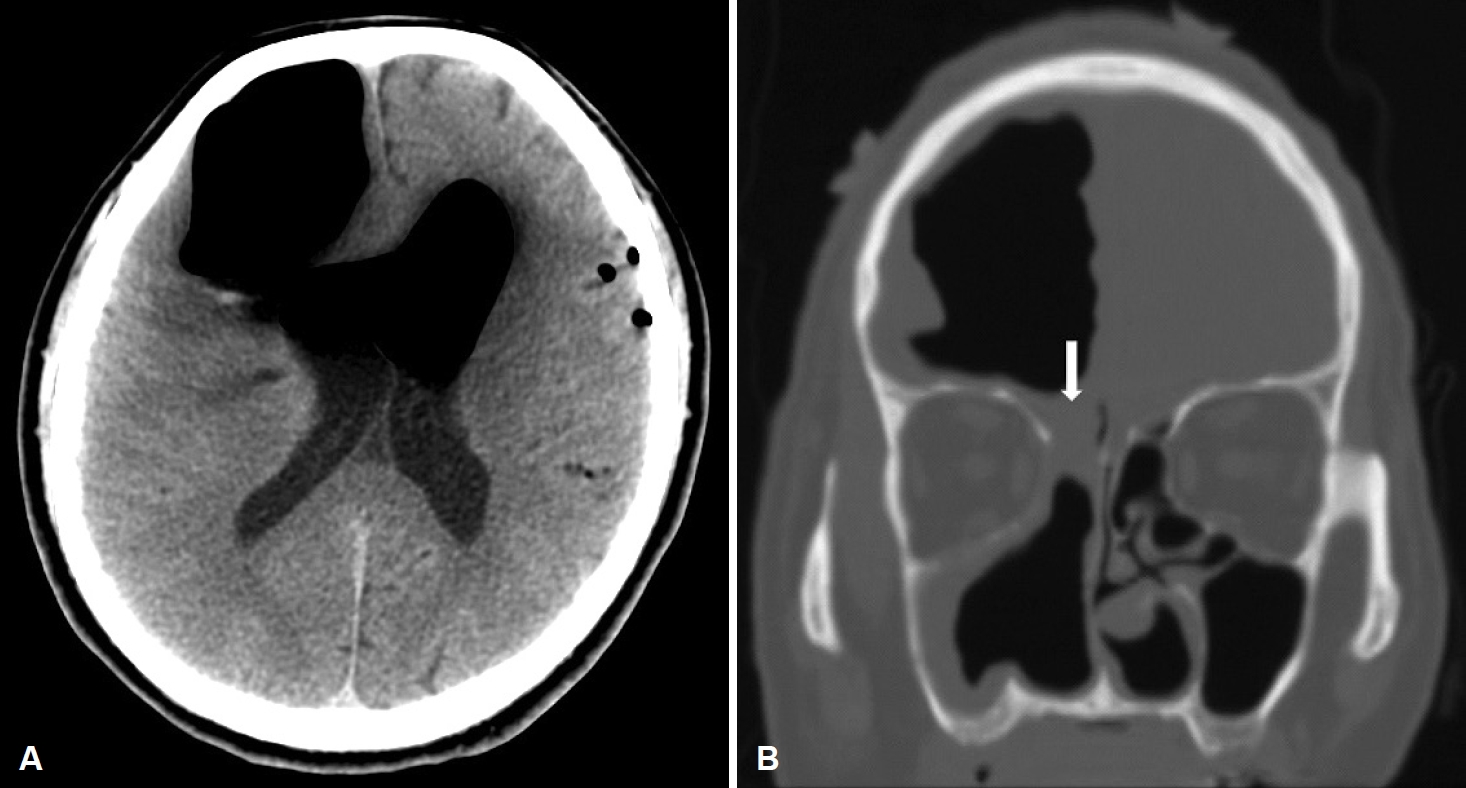

In the emergency room, he was found to be confused, but was following commands, and was oriented to person and place. On neurologic examination, his Glasgow Coma Scale score was 15. He showed normal pupillary reflexes, normal motor and sensory functions in all 4 extremities, normal deep tendon reflexes. A non-contrast CT scan of his brain was performed, and it showed significant air collection in the right frontal area and also a midline shift (Fig. 3). He was diagnosed with a tension pneumocephalus and referred to the neurosurgery department. Then, he underwent a bifrontal craniotomy for tension pneumocephalus. During the operation, we found adhesions between the nasal mucosa and dura mater, but there was no defect between nasal mucosa and dura and no CSF leakage. After detaching these adhesions, duroplasty and cranioplasty were performed. Postoperative conservative treatment was applied, including bed rest, meningitis prophylaxis, maintenance of extraventricular drainage. In the follow-up CT taken at 2 weeks after the surgery, resolution of tension pneumocephalus was observed (Fig. 4). His condition was stable and he showed a normal mental status, not confused. He was discharged 14 days after the surgery. In an endoscopic examination performed in the 2nd month, there was no skull base defect or CSF leakage (Fig. 5). The patient did not have any complaints or symptoms for 6 months after the surgery.

NotesAuthor Contribution Conceptualization: Jin Kook Kim. Data curation: Hansol Kim, Taesik Jung. Formal analysis: Hansol Kim, Taesik Jung, Jin Kook Kim. Methodology: Jin Kook Kim. Project administration: Joon Yong Park, Jin Kook Kim. Supervision: Jin Kook Kim. Visualization: Hansol Kim, Taesik Jung. Writing—original draft: Joon Yong Park. Writing—review & editing: Jin Kook Kim. Fig. 1.In the CT scan of paranasal sinuses, the right maxillary sinus was filled with a heterogeneous soft tissue mass. The mass was extending into the nasal cavity with widening of the maxillary ostium. Fig. 2.Endoscopic finding of the dural repair site. There was no cerebrospinal fluid leakage at postoperative 6 weeks. REFERENCES1. DelGaudio JM, Ingley AP. Treatment of pneumocephalus after endoscopic sinus and microscopic skull base surgery. Am J Otolaryngol 2010;31(4):226-30.